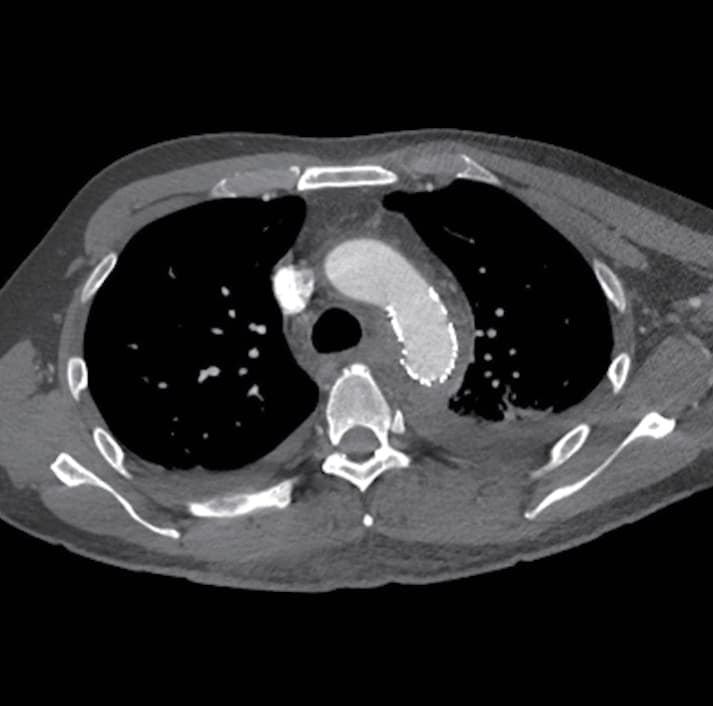

症例は45歳男性で列車事故のため受傷し救出されたが、意識は清明であるものの血圧60台のショック状態で、現場から救急搬送された。当院での造影CTでは近位下行大動脈損傷による破裂と周囲の縦隔血腫を認めた。他には恥坐骨と手の骨折を認めるのみで、頭部、腹部に外傷を認めなかった。緊急輸血を行いつつステントグラフトによる治療を行う方針となった。

術前のサイジングで中枢ランディング径は25 mmであり、左鎖骨下動脈から大動脈損傷部までのランディング長は小弯側の測定で18 mmであった。外傷により損傷されている部位の長軸方向の長さは40 mm程度であるが、その遠位の下行大動脈は壁内血腫様の所見であった。遠位ランディング径は21-23 mmであり、ステントグラフトは28 mm-15 cmを使用することとした。